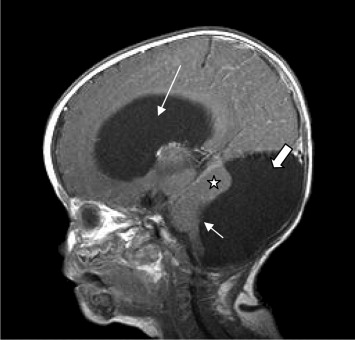

Dandy Walker Syndrome merupakan suatu sindrom (kumpulan gejala) yang terjadi pada seorang anak akibat tidak terbentuknya “pintu keluar” cairan otak dari dalam kepala. Dalam bahasa medis, pintu keluar ini disebut dengan suatu lubang khusus yaitu yang dinamakan dengan “Foramen Luschka dan Magendie”. Dalam teorinya, cairan otak manusia tersebut berada di dalam rongga cairan otak yang setiap hari diproduksi di dalam kepala dan setiap hari juga dibuang ke tubuh kita. Pada kondisi tertentu terjadi gangguan aliran cairan otak tersebut sehingga terjadilah penumpukan cairan otak yang disebut dengan “Hidrosefalus”. Hal ini akan berdampak terjadinya pembesaran rongga cairan otak yang akan menekan jaringan otak di sekitarnya. Pada Dandy Walker Syndrome, tidak terbentuknya pintu keluar ini yang mengakibatkan gangguan aliran cairan otak, pembesaran pada rongga cairan otak di sekitar otak kecil (ventrikel IV), disertai pula dengan terbentuknya kista besar di daerah otak kecil (serebelum), sehingga sebagian otak kecil (bagian tengah dari otak kecil) kemudian tidak tumbuh. Tidak tumbuhnya ini kemungkinan karena terhambat oleh kista berisi cairan otak yang menumpuk tersebut.

Penderita Dandy Walker Syndrome dapat disertai dengan hidrosefalus atau juga tidak. Dari beberapa rujukan menunjukkan angka sekitar 70-80% penderita Dandy Walker Syndrome juga disertai dengan hidrosefalus. Hidrosefalus ini disebabkan oleh gangguan aliran cairan otak seperti yang saya jelaskan diatas.

Tindakan bedah saraf yang dilakukan untuk penderita Dandy Walker Syndrome adalah dengan pemasangan selang pintasan dari daerah otak kecil (tempat kista berada) ke perut, disebut juga dengan “Cystoperitoneal shunt”. Bila terdapat hidrosefalus, maka dipasang juga selang pintasan dari rongga cairan otak menuju rongga perut (Ventriculoperitoneal shunt; VP SHUNT). Pemeriksaan oleh bidang spesialistik lain sangat diperlukan untuk mencari kemungkinan gangguan pada sistem organ yang lain, dan terapi harus dilakukan bila memang terindikasi.